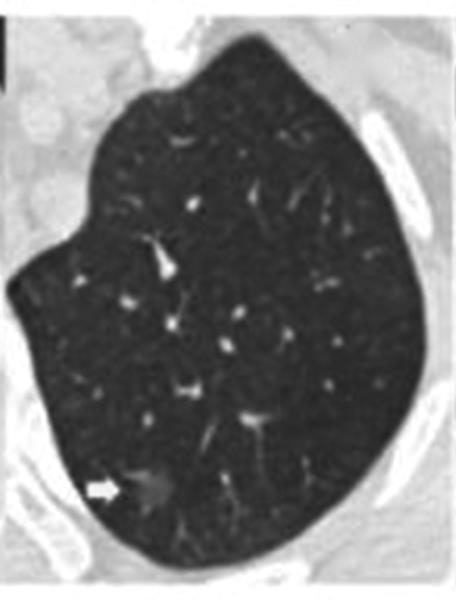

• 纯磨玻璃结节肺腺癌CT征象与其浸润程度的相关性分析及预测模型构建

2023, 48(4):423-429. DOI: 10.13406/j.cnki.cyxb.003200

摘要 (138) HTML (44) PDF 1.10 M (286) 评论 (0) 收藏

摘要:目的 探究纯磨玻璃结节(pure ground-glass nodule,pGGN)肺腺癌计算机断层扫描(computed tomography,CT)征象与其浸润程度的相关性,建立CT征象与浸润程度的预测模型。方法 回顾性分析424例经手术切除、病理活检证实且胸部CT表现为pGGN的肺腺癌患者临床资料及CT征象,根据病理活检结果分为非典型腺瘤样增生、原位腺癌、微浸润腺癌和浸润性腺癌4组,对组间差异采用卡方检验或Fisher确切概率法进行统计分析。对有统计学意义的结果,使用怀卡托智能分析环境(Waikato environment for knowledge analysis,WeKa)中的6种学习算法进行预测模型构建,并验证准确性,挑选出最适用于本研究的预测模型。结果 4组间在结节直径、结节密度值上的差异具有统计学意义(P<0.001),对应的直径平均值分别为6.90、8.65、10.71、14.56 mm,对应的密度平均值分别为-633.16、-543.04、-401.03、-322.94 HU,随着病灶的浸润程度加重,结节的直径及密度值呈现明显的上升趋势。4组间在结节边界、分叶、毛刺、血管穿行、胸膜凹陷、空气支气管征、空泡征等的差异具有统计学意义(P<0.05),而结节的生长位置,年龄、吸烟史、直系亲属肺癌家族史等差异无统计学意义(P>0.05)。随机森林算法所构建的模型预测准确率为76.42%~79.72%,Kappa系数为0.597~0.670,受试者工作特征(receiver operating characteristic,ROC)曲线下面积均大于0.9,在误差指标中表现最优,是最适合于本研究的预测模型。结论 pGGN的不同CT征象与其浸润程度密切相关,可以用于建立预测模型。基于随机森林算法所建模型,在有创干预前早期快速识别pGGN浸润程度的平均准确率为78.07%,准确度最高,对肺癌预测具有潜在应用价值。

• 0+1

• 1+1

• 2+1

• 3+1

• 4+1